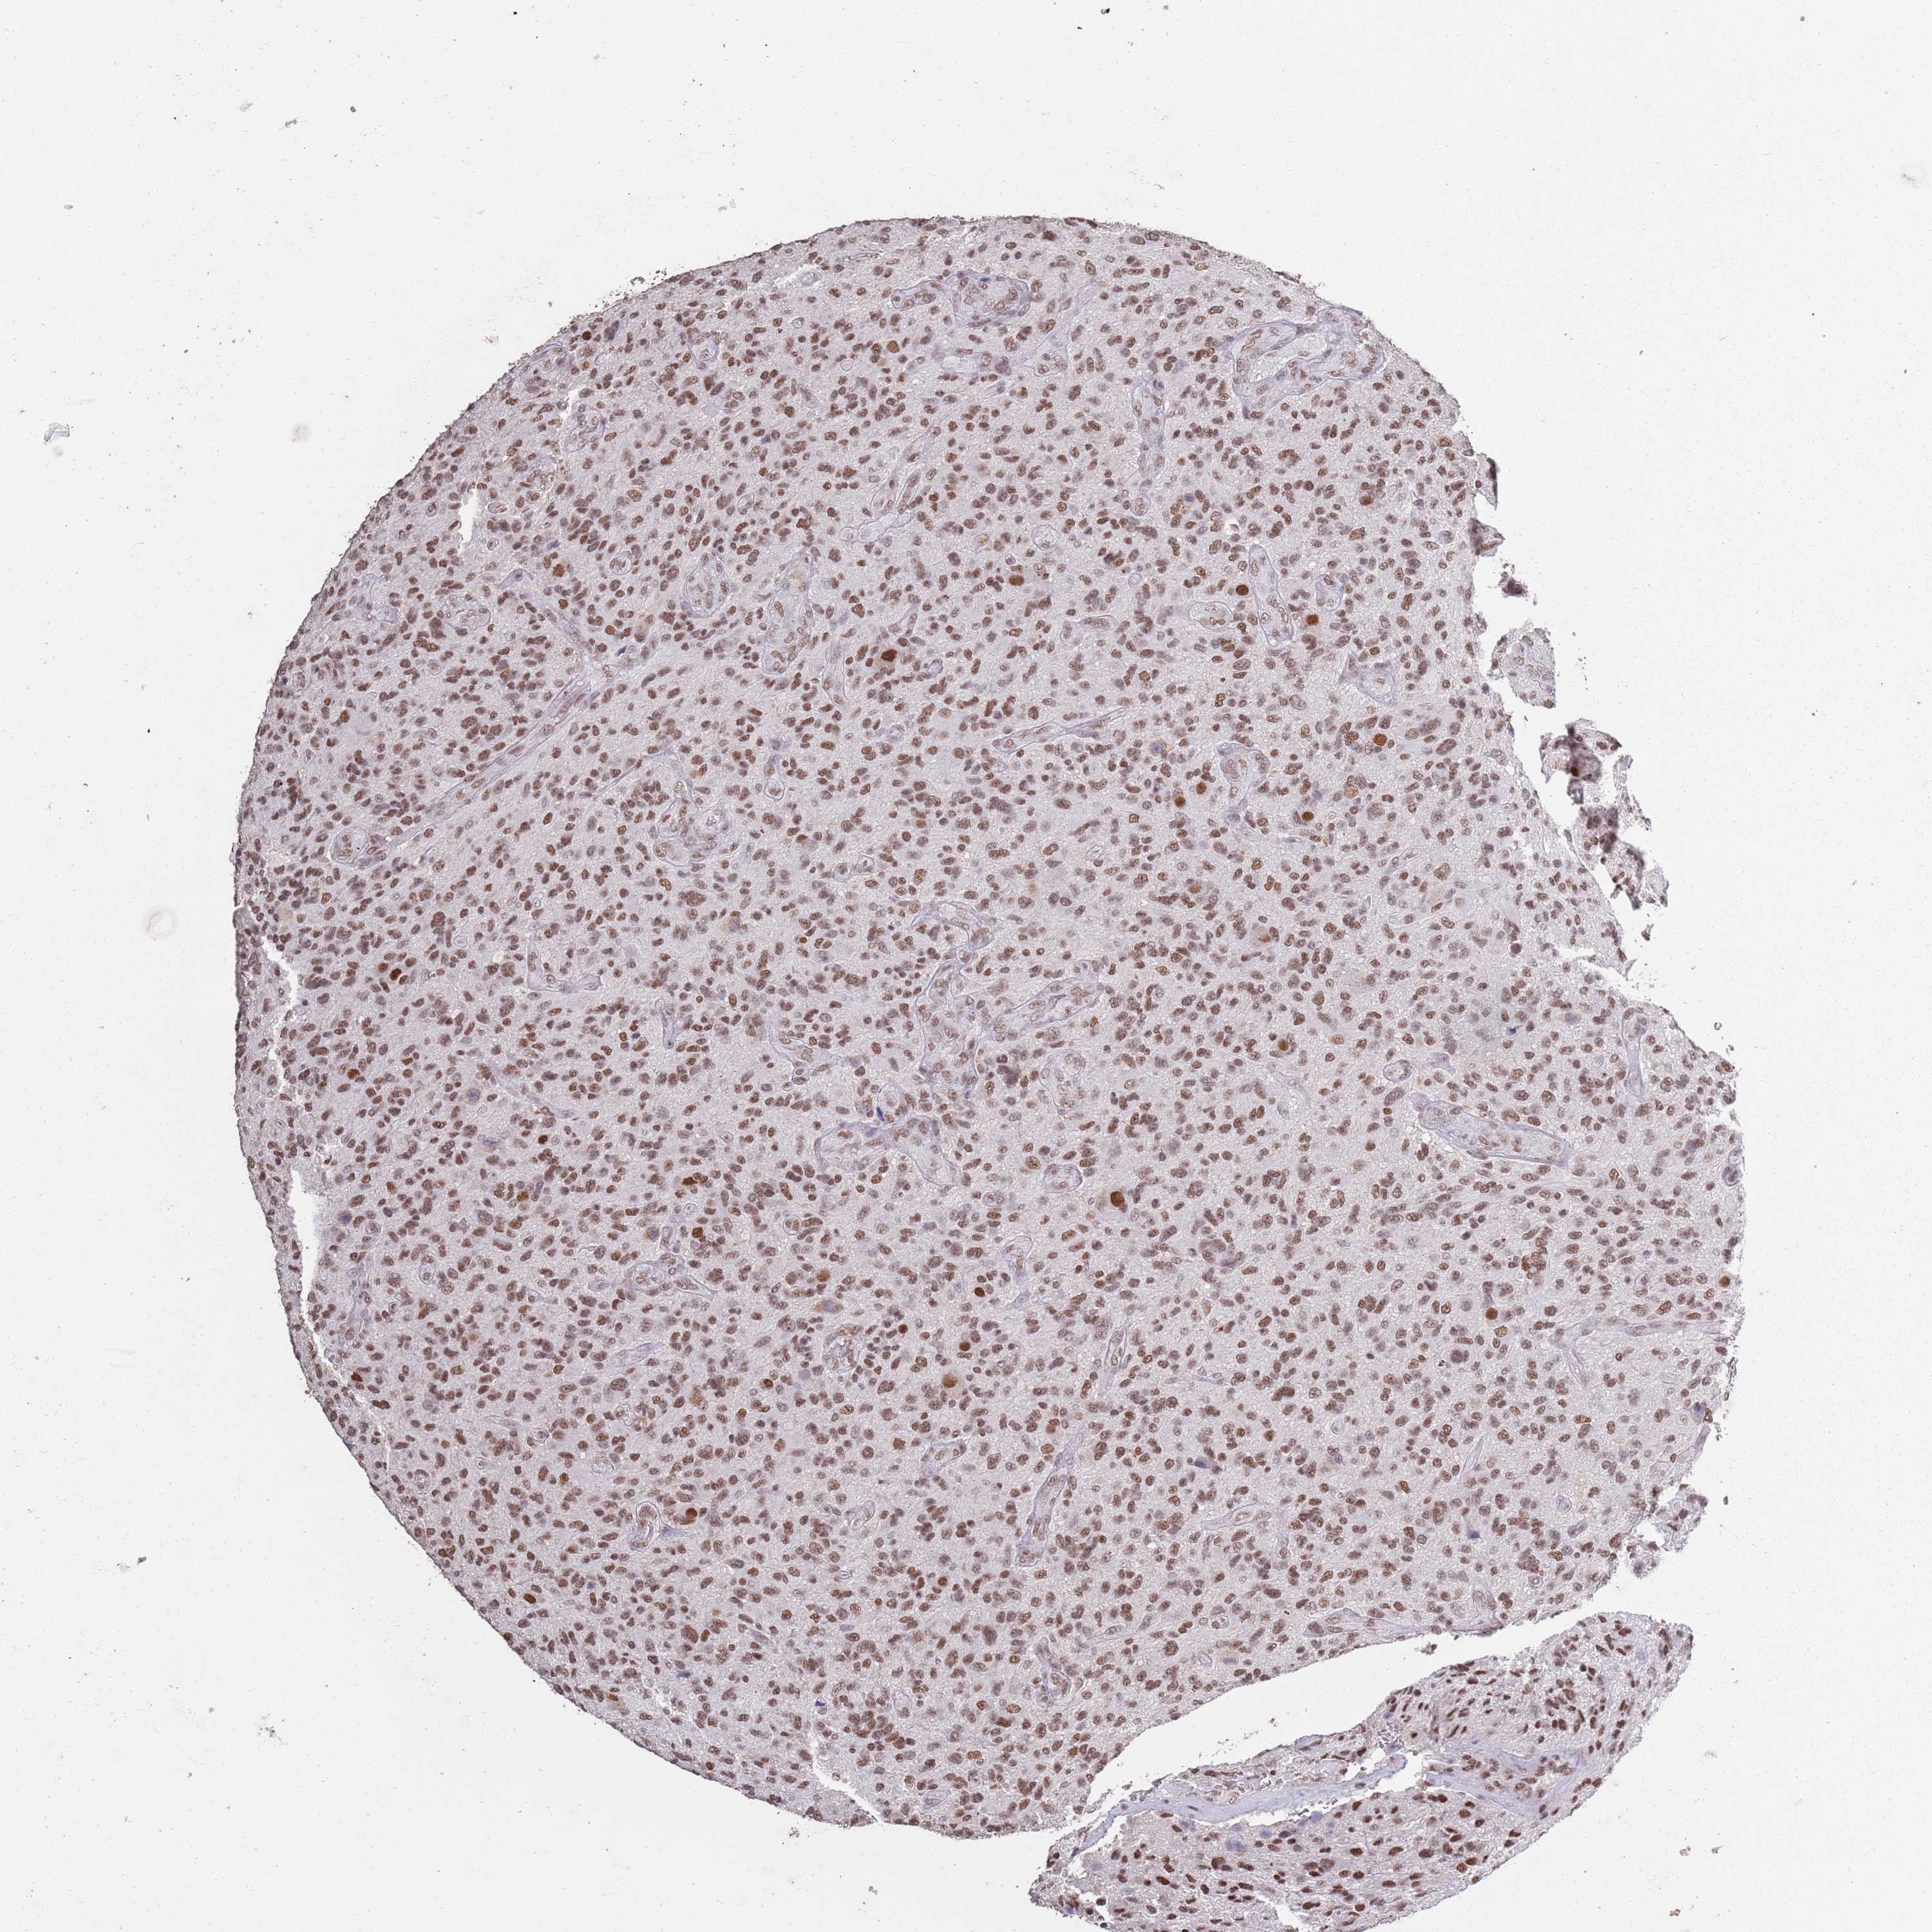

GLIOMA - Protein expressioni

A mouse-over function shows sample information and annotation data. Click on an image to view it in a full screen mode. Samples can be filtered based on level of antibody staining by selecting one or several of the following categories: high, medium, low and not detected. The assay and annotation is described here.

Note that samples used for immunohistochemistry by the Human Protein Atlas do not correspond to samples in the TCGA dataset.

Antibody stainingi

Antibody staining in the annotated cell types in the current human tissue is reported as not detected, low, medium, or high, based on conventional immunohistochemistry profiling in selected tissues. This score is based on the combination of the staining intensity and fraction of stained cells.

Each image is clickable and will lead to virtual microscopy that enables deeper exploration of all samples and also displays staining intensity scores, fraction scores and subcellular localization as well as patient and tissue information for each sample.

Antibody HPA039634

Antibody HPA048127

Staining

High

Medium

Low

Not detected

Intensity

Strong

Moderate

Weak

Negative

Quantity

>75%

75%-25%

<25%

None

Location

Nuclear

Cytoplasmic/membranous

Cytoplasmic/membranous,nuclear

Glioma, malignant, High grade

Glioma, malignant, Low grade